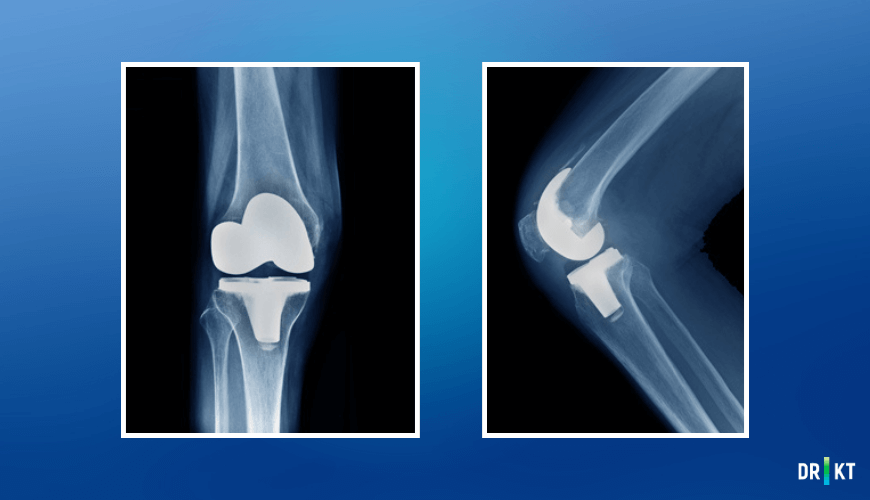

Diz protezi ameliyatı, hasarlı veya aşınmış eklem yüzeylerinin çıkarılarak metal alaşım ve polietilen plastik parçalardan oluşan yapay bir eklemle değiştirilmesi işlemidir. Ameliyatın temel amacı, hastanın ağrılarını gidermek, diz fonksiyonlarını iyileştirmek ve günlük aktivitelere rahat bir şekilde dönüş sağlamaktır.

Ameliyat türü, dizde oluşan hasarın yaygınlığına göre belirlenir. Eğer diz ekleminin tamamı etkilenmişse total diz protezi, yalnızca bir bölümü etkilenmişse kısmi (unikondiler) diz protezi tercih edilir. Her iki yöntemde de hasta memnuniyeti son derece yüksektir ve modern cerrahi tekniklerle yapılan ameliyatların başarı oranları oldukça etkileyicidir.